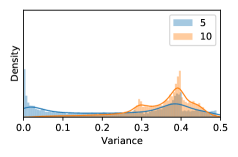

To model how different classifiers will respond to a given input , we assume that the prediction from classifier is sampled from a beta distribution that is characterized by two parameters by and . We further assume that is fixed to the same constant value for all ’s. Under this assumption, each input can be described by ( can be calculated since is fixed), easing further analysis. The Severity Level (SL) of the case represented by image can be characterized by the parameter . The larger the value of , the more severe the case of is. When and are close, the case is ambiguous as the distribution shifts towards being symmetric (i.e. signifying much disagreement among classifiers) rather than being one-sided (i.e. consensus among classifiers that is negative or positive). We provide a set of examples in Figure 2 and also Figure S.8 in the supplementary materials showing how the beta distribution can be used to capture diverse predictions given by an ensemble learner.

5.1 Distribution of Uncertainty Scores

Distribution of Uncertainty Scores Across Different Severity Levels As explained in Section 3, each uncertainty metric essentially defines an order/ranking among the data points. We conducted an analysis to better understand what data will be assigned high uncertainty under a particular uncertainty metric . Picking out the highest ranked data points (), we calculated the ratio of data points from each SL. Figure 4 summarizes the results as box plots for the Kaggle-DR and the Messidor-2 datasets; additional detailed statistics can be found in Table S.1 in the supplementary materials. From the plot and table, SL1 & SL2 examples account for a higher proportion among the top-ranked uncertain examples across the three ensemble methods. This finding matches our intuition that incipient disease examples (SL1 & SL2) are more likely to be considered uncertain by ensemble methods due to their ambiguity.

In contrast, the MC-dropout method showed the worst overall performance among the three, as it can be seen from the high ratios of SL0 examples among the uncertain negatives in Figure 4. The histograms in Figure 2 provides another perspective to look into the phenomenon, where a decent proportion of MC-dropout model’s predictions on SL0 inputs entailed low confidence (far from 0 or 1), which from another angle explained why MC-dropout was less specific in terms of lower FNP; many no-DR inputs (i.e. SL0) were erroneously assigned high uncertainty by MC-dropout models.

As discussed in Section 5.1 and Section 5.3 in the main paper, the mean metric and the stacking ensemble will have better performance in the precision (specificity) on the ambiguous data. Here, more detailed results are shown in Figures S.3 & S.6 and Table S.1. Figures S.3 & S.4 show the histograms of the uncertainty score for Kaggle-DR and Messidor-2 datasets that are the in-distribution (i.d.) dataset in our experiment and FigureS.5 & S.6 show the histograms for ImageNet and CIFAR-10 datasets, which is the o.o.d. datasets in our experiment. Each group of histograms contains results from the three evaluated ensemble methods (stacking ensemble, MC-dropout and TTA) and the three uncertainty metrics (mean, var and kl). Additional detailed results not displayed in Figure 4 can be found in Table S.1, which shows the proportion of the data of different SLs varies across different . For comparison, we also included in Table S.1 the results from single learners, and the proportions of data of different SLs (before any selection was made).